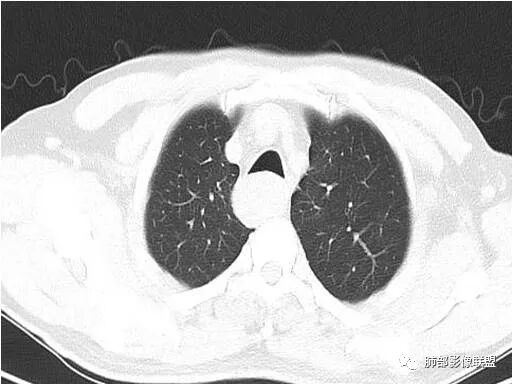

晨读:男性,体检发现右后纵隔占位,CT示右后纵隔梭形软组织肿块,局部与食管壁分界不清,压迫气管与食管,平扫密度均匀,增强轻度不均匀渐进性强化,内部可见片状低密度区,考虑为1、食管来源平滑肌瘤。2、神经鞘瘤

2.定位:右后上纵隔肿块,与食管关系密切,边缘光滑,冠状位显示肿块与食管壁结构相顺延,上下径大于横径,呈现跨管壁内外生长倾向,食管管腔狭窄,而气管腔内未见突入,因此食管来源肿块可能大。